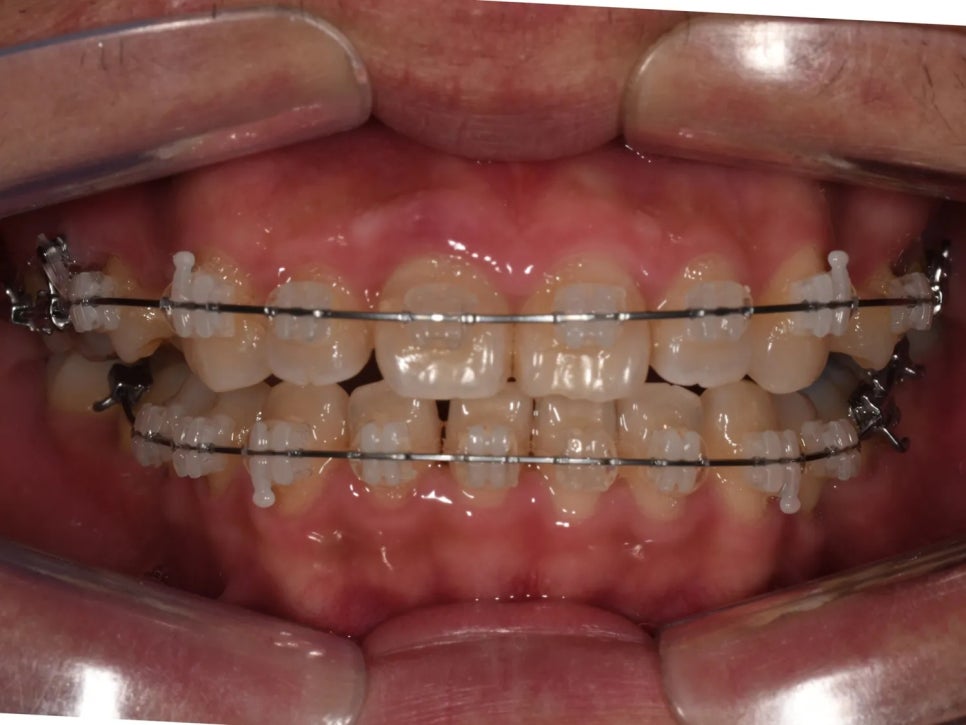

치료 완료 – 돌출입 개선, 정상 교합 형성, 가지런한 치열

드디어 교정 장치를 제거하고 최종 결과를 확인하였습니다.

치열이 정말 가지런하게 배열되었고, 환자분이 가장 원하셨던 돌출입도 예쁘게 개선되었습니다. 옆모습이 크게 달라졌습니다.

무엇보다 중요한 건, 오른쪽 교합이 정상적으로 물리게 되었다는 점이라고 할 수 있습니다. 턱을 왼쪽으로 틀어서 물어야 했던 불편함이 해소됐고, 과개교합도 개선되어 위아래 앞니가 물리는 깊이가 정상 범위로 돌아왔습니다.

편하게 무는 모습이 느껴지십니까?

처음에 돌출입 하나로 오셨지만, 종합적인 진단을 통해 교합(기능) + 심미성 + 장기적 건강 모두를 개선할 수 있었던 케이스였습니다.